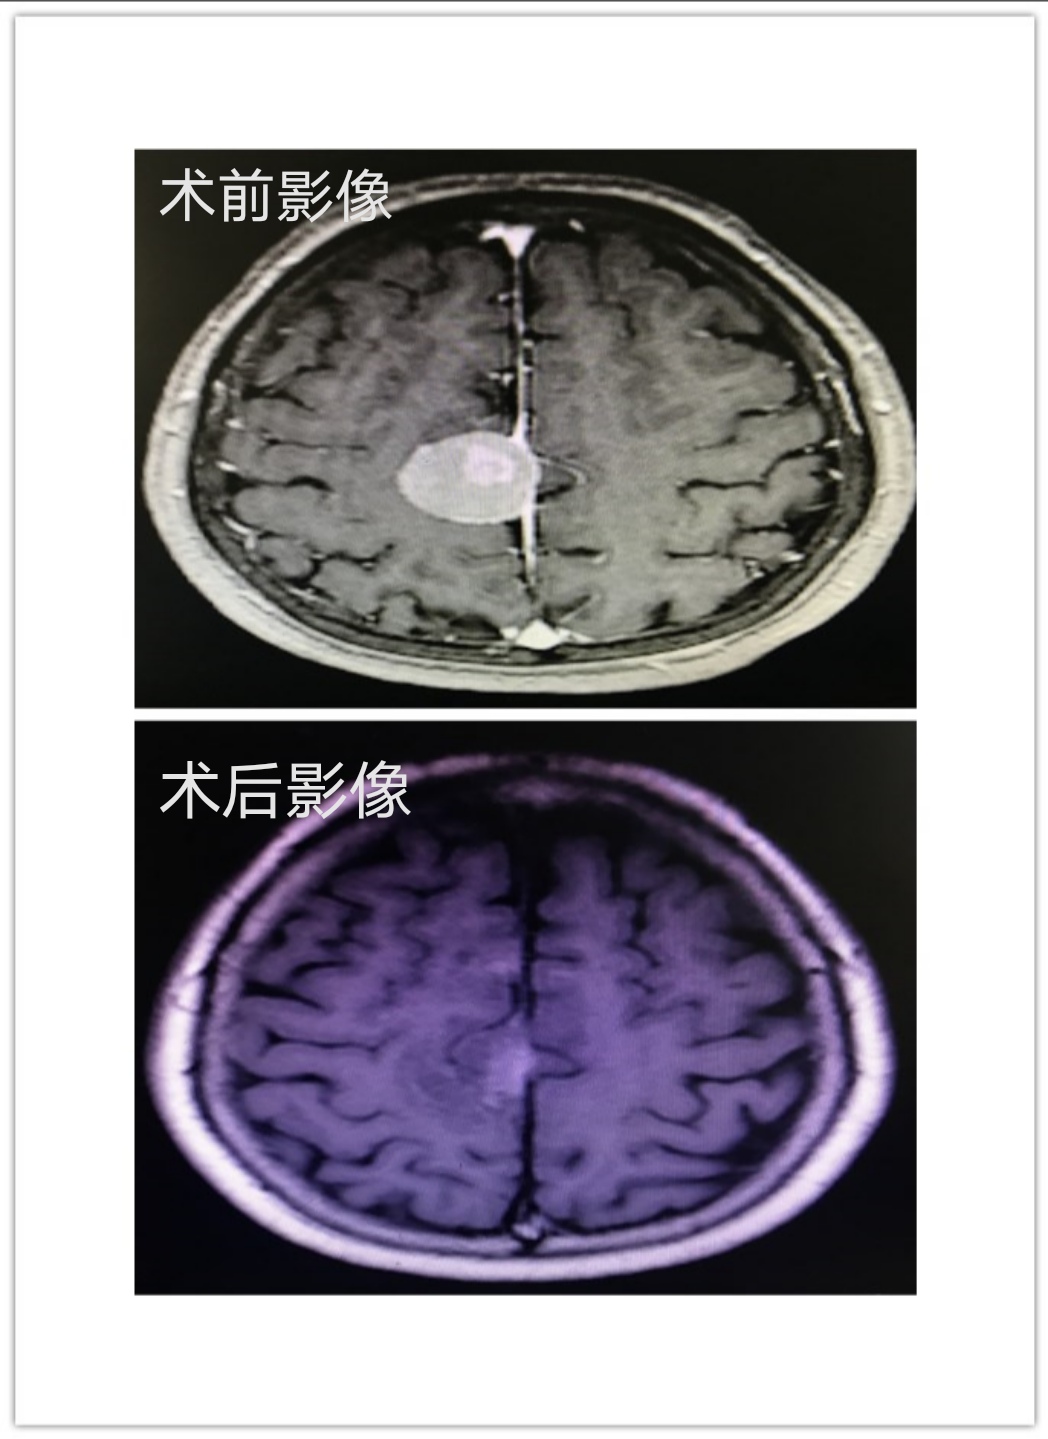

近日,郑阿姨因头晕伴视物旋转3天,左下肢肌力减退入院治疗。MRI检查发现脑膜瘤体积进一步增大,瘤周压迫、水肿效应明显,这意味着如果不实施手术,她将在越来越大脑膜瘤压迫下渐渐走路不稳,甚至还可能会左腿瘫痪。为了获得更佳的生存质量郑阿姨决定接受手术治疗。

神经外科黄聪曦主任医师迅速组织以福建医科大学附属第一医院神经外科江常震教授为首的神经外科医疗团队与手术麻醉科相关医护人员进行严谨的术前讨论,制定详细周密的手术方案。最终江常震教授、黄聪曦主任医师、谢建民主治医师、方荣臻主治医师,采用额部切口,小骨窗开颅,应用Storz神经内镜,避开脑功能区,应用射频刀切除质硬的肿瘤,减少对脑组织的热损伤,顺利将患者颅内肿瘤完整切除。术后病理报告:符合WHO1级脑膜瘤。CT和MRI复查肿瘤已完全切除。